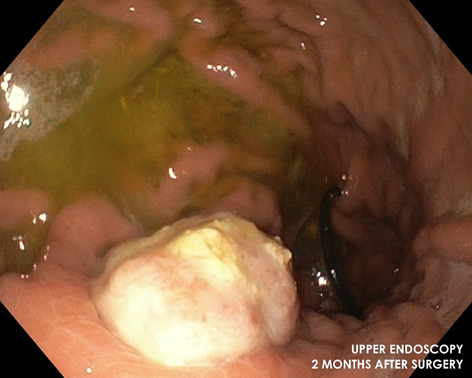

Result: The comparative analysis of the data shows a decrease in the number of presentations in ESU of AC cases during the pandemic, compared to the previous year, most often due to patients' fear of contacting the virus in the hospital environment. The median time between the onset of symptoms and the presentation in the ESU: 2020 – 14 days, 2019 – 5 days. Forms of moderate and severe AC predominated in the pandemic: GradeI—14.28%; GradeII—57.14%; GradeIII—28.57%. In 2019 GradeI—66.39%, GradeII—27.73%, GradeIII—5.88%. Laparoscopic cholecystectomy was attempted for all patients from the beginning, but the complications identified during surgery and severe forms led to a conversion rate in 2020 of 14.28%, compared to 5.88% in 2019. The severity of the cases is also observed in the postoperative complications encountered (perihepatic abscess Fig. 2. Figure 2, wound infection, bile leak; 2019—5.04%, 2020—23.21%), which required surgical reinterventions to solve them (2019: 2.52%, 2020: 10.71%). The number of deaths was significantly higher in 2020 (5.35%), compared to 2019 (0.84%).